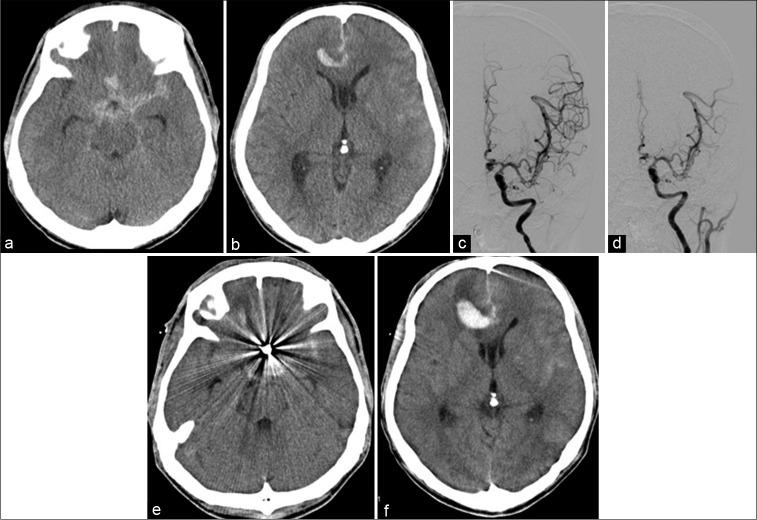

Whether hematoma expansion after aneurysmal rupture is always a sign of rerupture remains unclear. Hence, the present study aimed to assess the incidence and risk factors of hematoma expansion unrelated to aneurysmal rerupture after endovascular embolization for ruptured cerebral aneurysms.

Hematoma expansion unrelated to aneurysmal rerupture occurred in 7 (10%) of 70 patients. Interestingly, four of seven patients had distal anterior cerebral artery (ACA) aneurysms. The interval from onset to aneurysm coiling was shorter in patients with hematoma expansion than in those without ( = 0.040).

Early embolization of ruptured ACA aneurysms might increase the risk of hematoma expansion unrelated to aneurysmal rerupture because the procedures were conducted under systemic anticoagulation. It would be better to refer the patient for direct clipping if the patient has a distal ACA aneurysm with parenchymal hematoma at interhemispheric fissure. Delayed coil embolization, which means around 12-18 h delayed, might be another option for ruptured distal ACA aneurysms to prevent hematoma expansion.